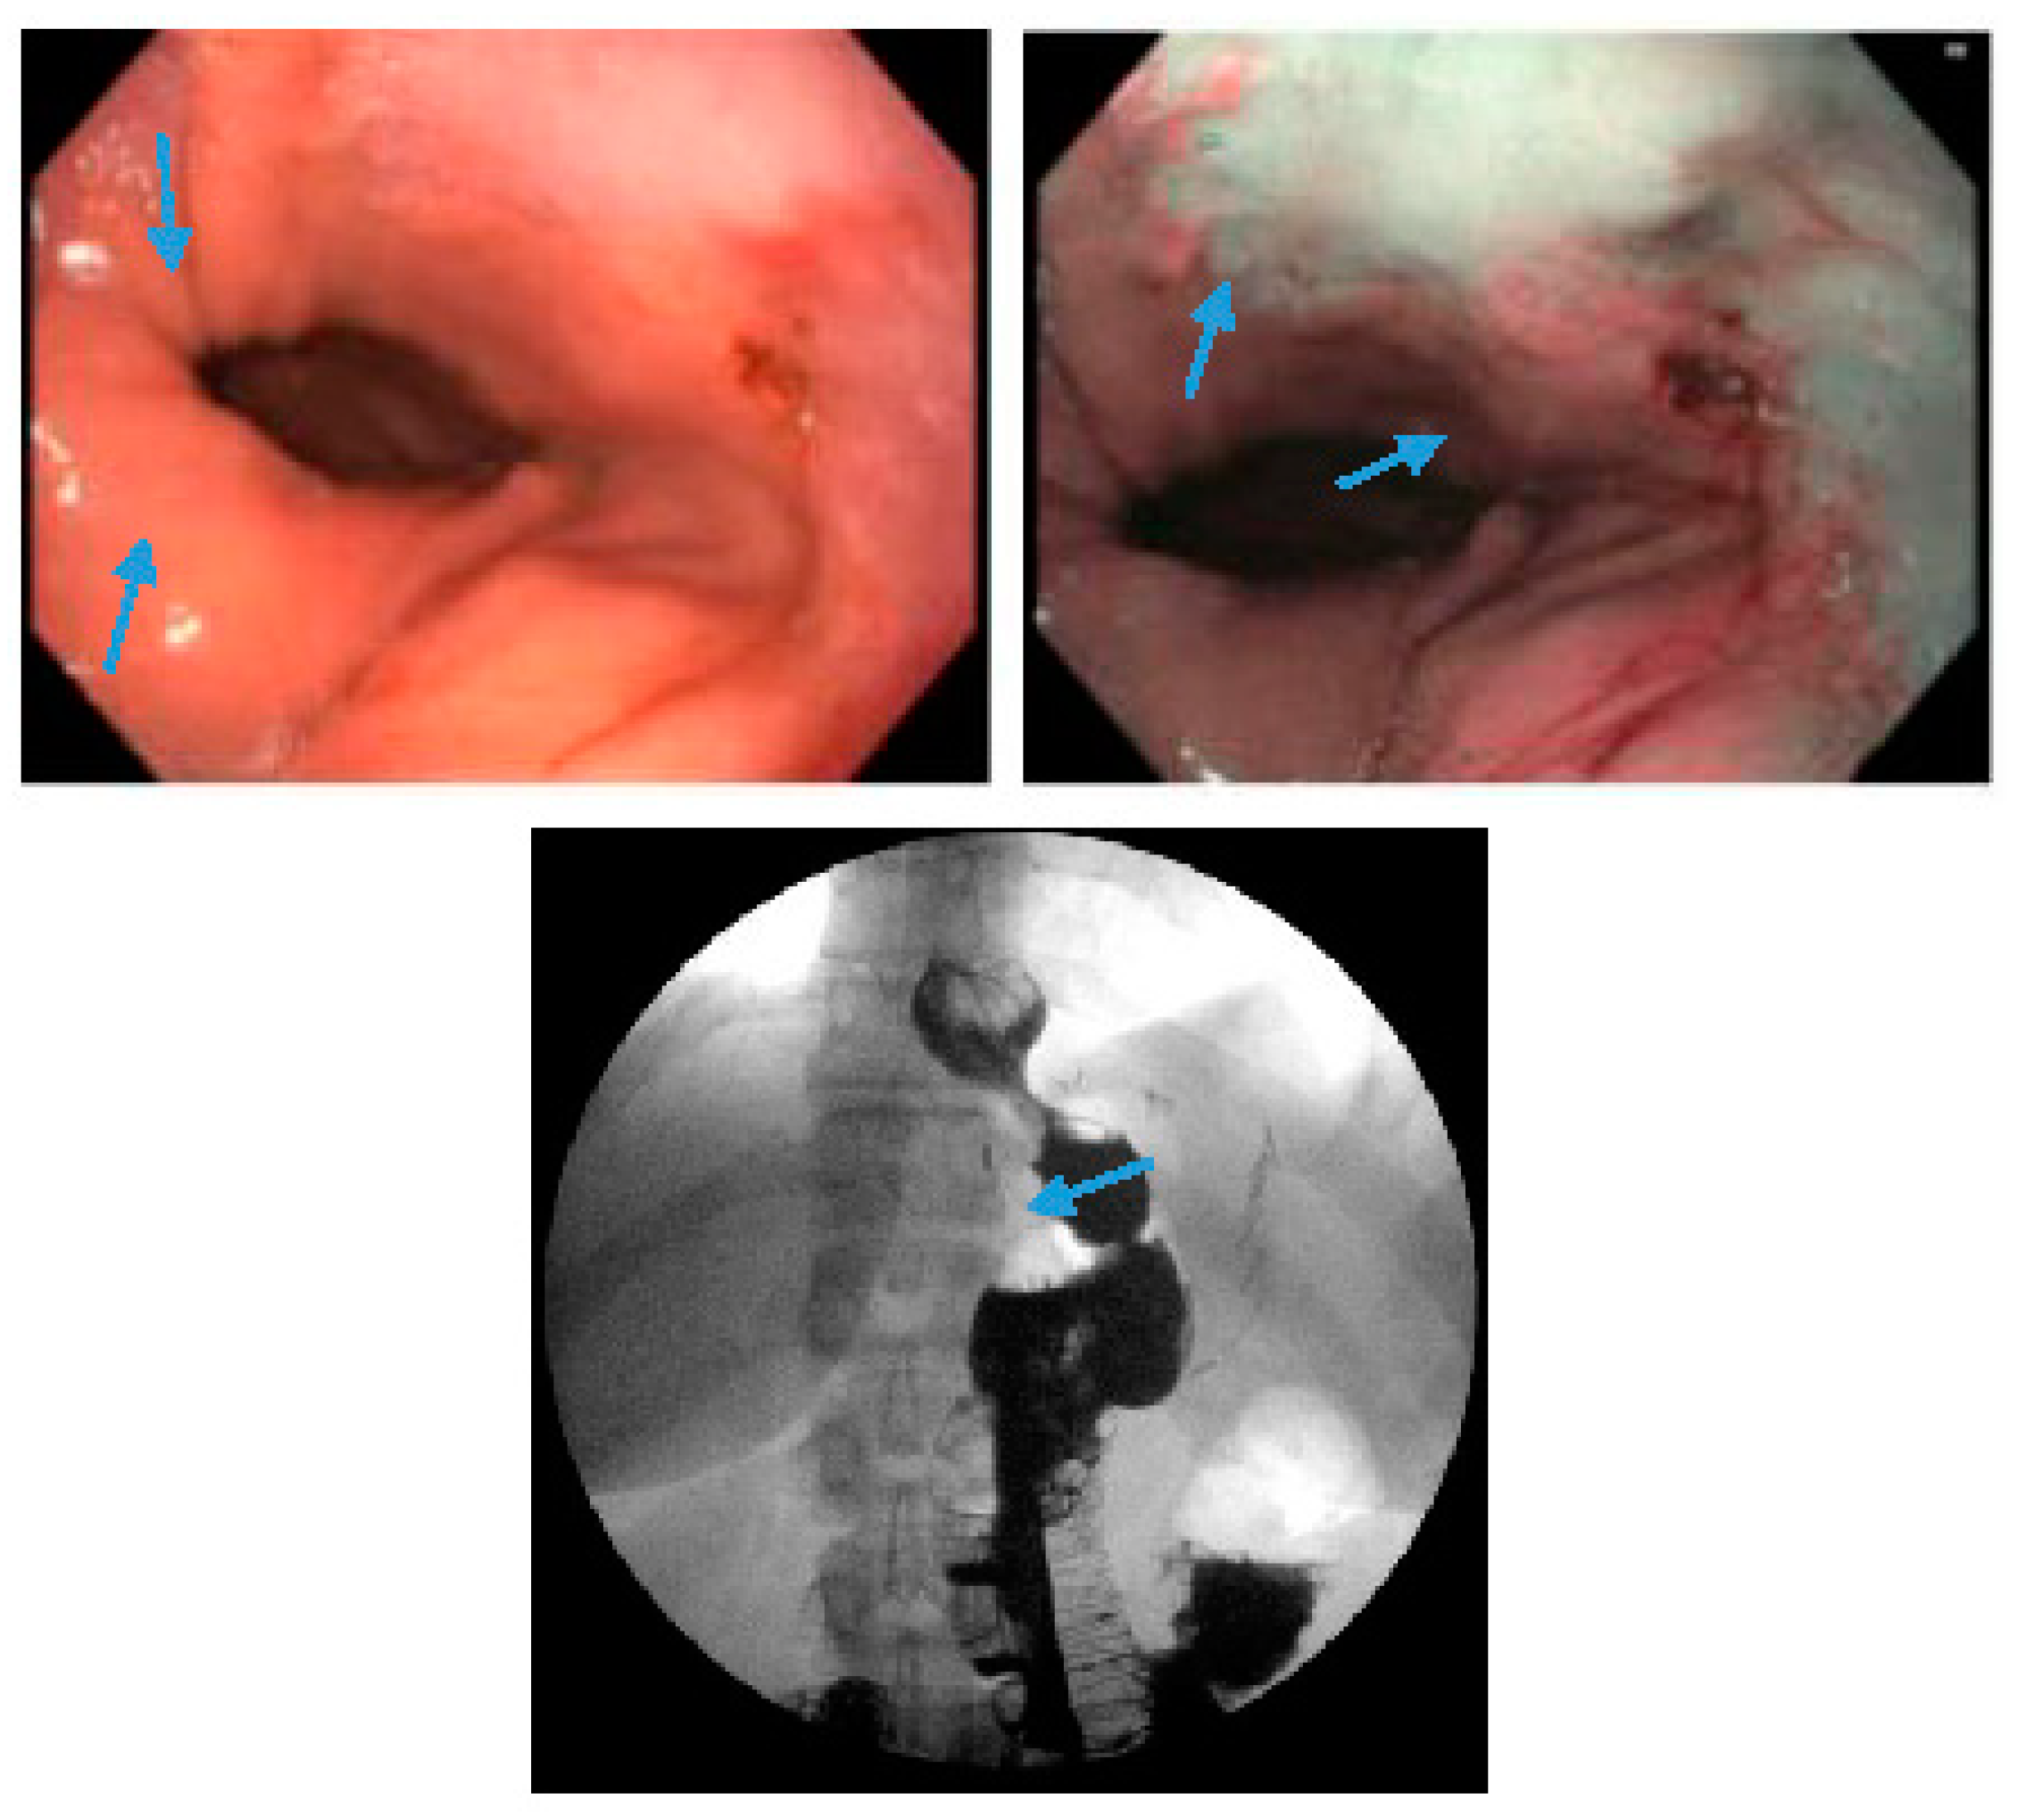

Figure 6. Endoscopic images reveal a 3-cm hiatal hernia (arrows, top left) and Los Angeles Grade B esophagitis (arrows, top right) in the lower-third of the esophagus with narrow-band imaging in a patient post-sleeve gastrectomy with symptoms of gastroesophageal reflux disease. The patient eventually required Roux-en-Y gastric bypass (arrow, bottom) and concomitant hiatal hernia repair as demonstrated on upper gastrointestinal series.